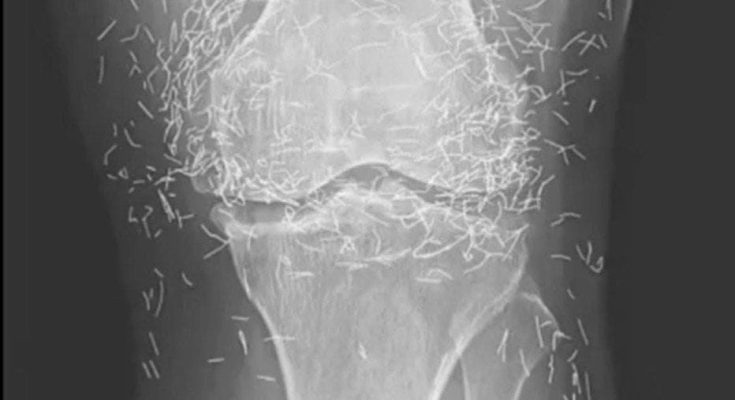

Years later, when doctors took X-rays to evaluate her knee condition, they weren’t prepared for what appeared on the images. Her knees were filled with dozens of bright, metallic flecks — tiny needles embedded deep within the joint area.

The findings were later documented in a case published by the New England Journal of Medicine.

Beyond inflammation, the needles created another problem: imaging complications. Metal objects can obscure parts of the anatomy on X-rays, making it harder for doctors to clearly assess joint damage or disease progression.

Even more concerning, the presence of metal inside the body can make certain scans dangerous. MRI machines rely on powerful magnetic fields, and embedded needles may shift during scanning, potentially damaging blood vessels or surrounding tissue. In short, future diagnostic options for this patient became limited.